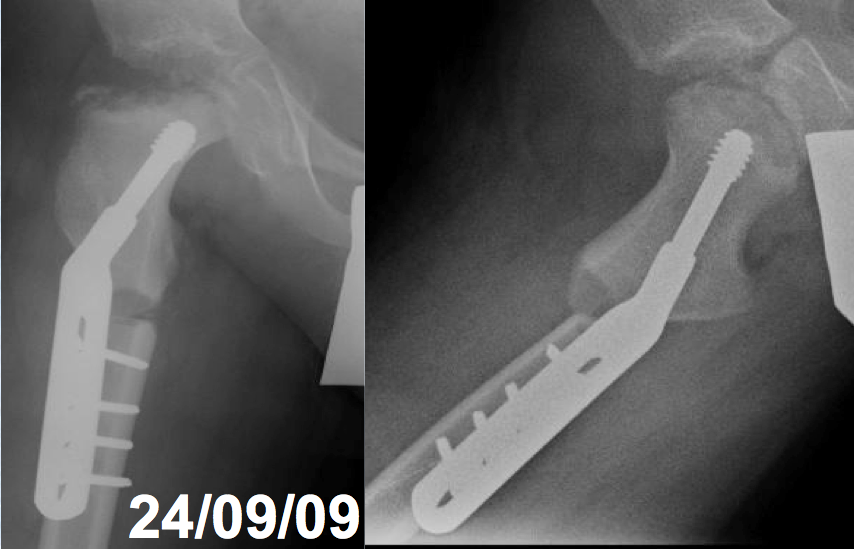

Enfermedad de Legg-Perthes-Calvé recurrente. Descripción de un caso y revisión de la literatura. [Recurrent Legg-Perthes-Calvé disease. A case report and literature review]